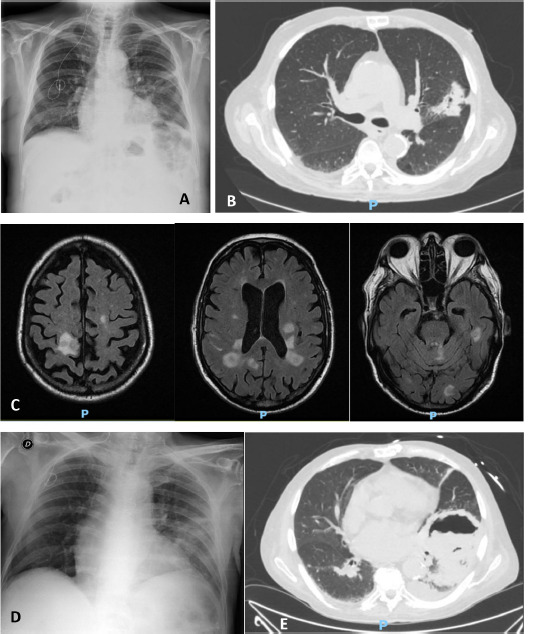

Nocardia and mucoral co-infection in heart transplant recipient.